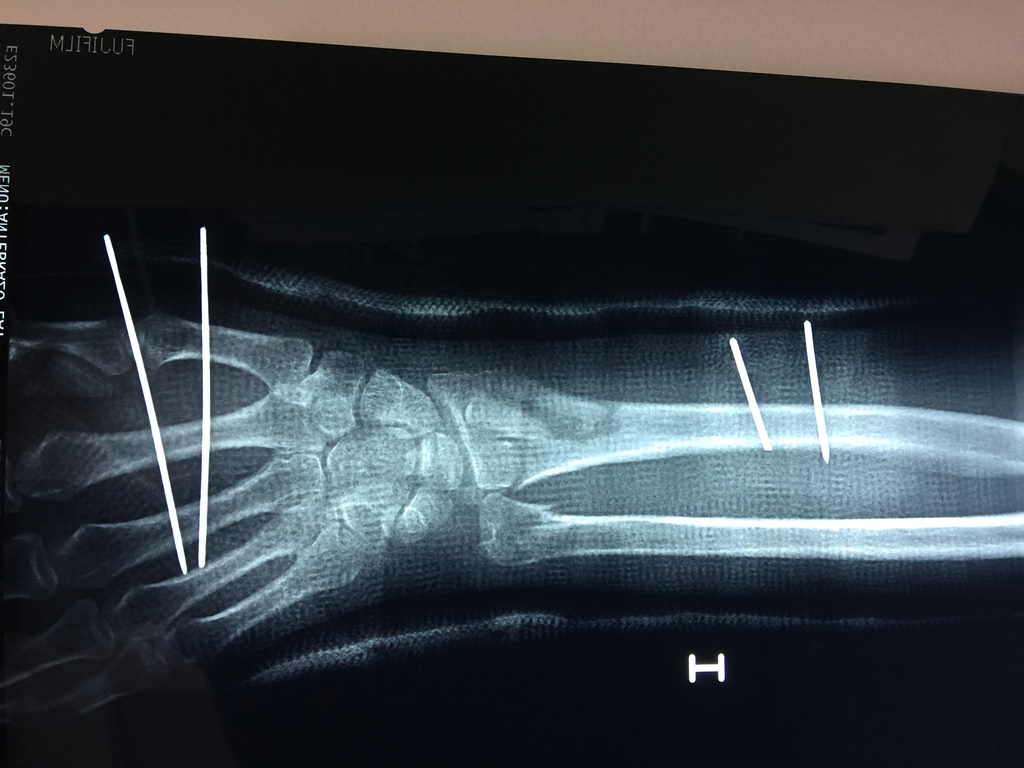

Cirugías de Húmero - Cirugías de Muñecas y Manos

Los procedimientos más comunes en cirugía de la mano son aquellos destinados a reparar traumatismos, incluyendo lesiones de tendones, nervios, vasos sanguíneos, y articulaciones; huesos fracturados; y quemaduras, cortes, y otros daños de la piel.